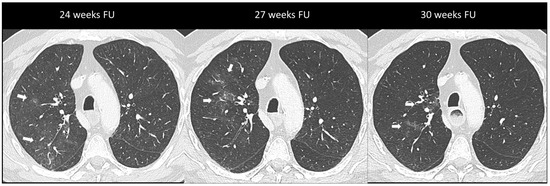

2.5.2. Ir-Thyroiditis

- Park, H.; Hata, A.; Hatabu, H.; Ricciuti, B.; Awad, M.; Nishino, M. Immune-Related Thyroiditis in Patients with Advanced Lung Cancer Treated with Immune Checkpoint Inhibitors: Imaging Features and Clinical Implications. Cancers 2023, 15, 649. [Google Scholar] [CrossRef] [PubMed]